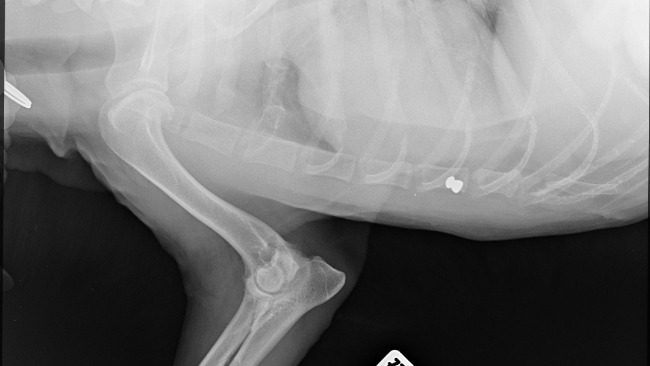

Ostatnie wizyty u specjalistów kompletnie mnie rozwaliły. U ortopedy prześwietlenia wykazały silne zmiany zwyrodnieniowe prawie wszystkich stawów, w tym te niezwykłe bolesne w bioderkach oraz zwichnięcie rzepki. Dlatego Jogi ma takie problemy z chodzeniem.

Ale na zdjęciach zobaczyłam coś znacznie gorszego, co rozwaliło mi serce na miliony kawałków. Ten biedak jest cały nafaszerowany śrutem. Jakiś zwyrodnialec strzelał do niewidomego psiaka, który nie wiedział, z której strony padały strzały i nawet nie był w stanie uciekać. CZY MOŻECIE WYOBRAZIĆ SOBIE TEN STRACH I CIERPIENIE ???!!!!!!!!!!!!!!!!!!!!! Jakim trzeba być zwyrolem i zarazem tchórzem, żeby strzelać do kalekiego, niewidomego zwierzaka.